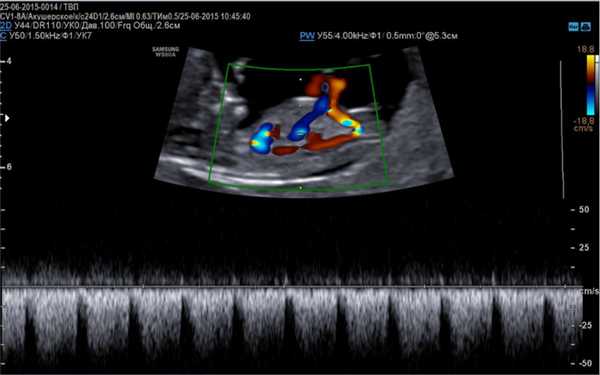

Основой для качественной диагностики является наличие программы, позволяющей определить функциональное состояние сердечно-сосудистой системы на приборе, оснащенным специальным датчиком, имеющим частоту сканирования не менее 5 МГц, а также цветное картирование системы кровообращения и доплер.

Эхо кг плода позволяет определить следующие параметры:

- частоту сокращений сердца;

- проходимость кровеносных сосудов;

- скорость и направленность движения крови по сосудам;

- соотношение объема поступающей и выходящей из аорты крови.

- Доплер эхокардиография, более расширенная методика, определяющая гемодинамику, ритмичность и сократительную способность сердца, направленность тока крови по сосудам.

Визуализация анатомических структур сердца плода при эхо кг

Данные виды исследования также позволяют оценить количество циркулирующей крови, степень сужения артерий, минутный выброс, что является важным диагностическим критерием в диагностике патологий сердца.